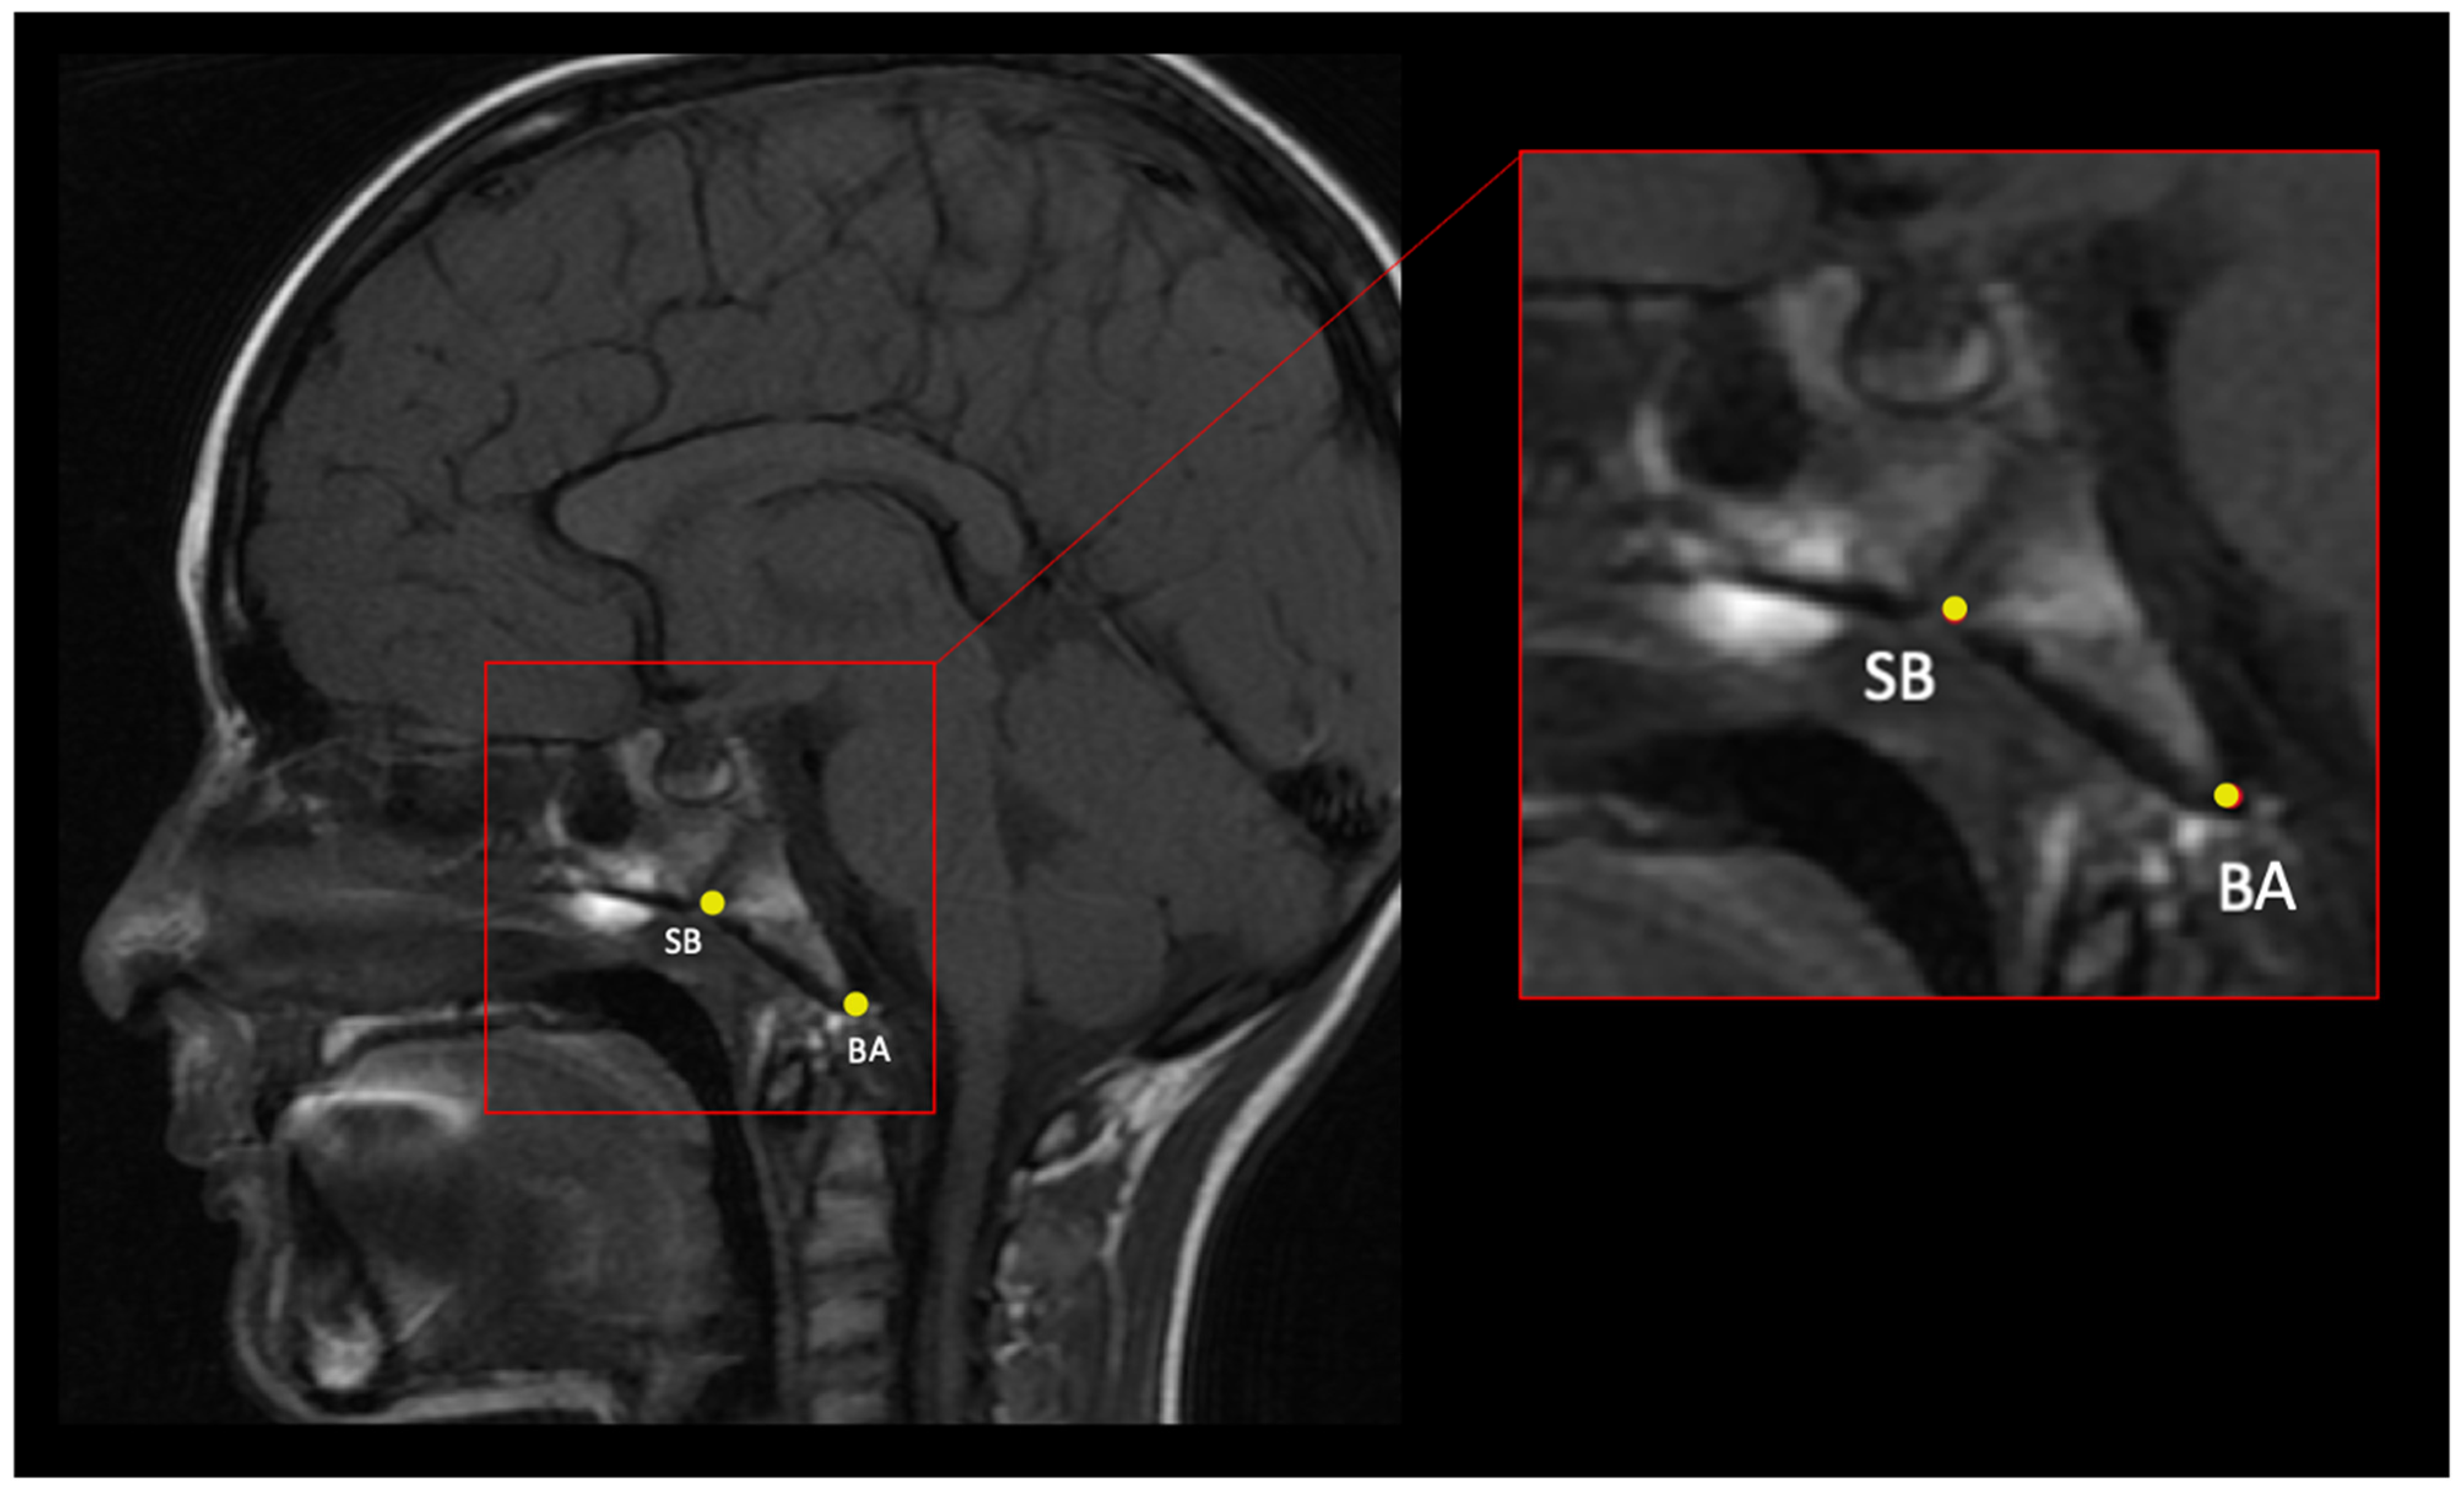

| Bone Landmark | Abbr. | Location | Definition | Description | Figure |

|---|---|---|---|---|---|

| Sphenobasion | SB | Midline | Midline of spheno-occipital synchondrosis | In a midsagittal plane, identify the clivus and place the landmark on the superior border of the clivus on the external surface in between the sphenoid and occipital bones; this is a cartilaginous plate in children. | Figure 2 |

| Basion (exo-basion) | BA | Midline | Midline of anterior foramen magnum | In a midsagittal plane, identify the most inferior–posterior point on the clivus. | Figure 2 |